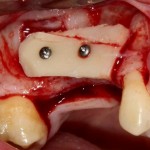

Рисунок 52, 53. Установка импланта через 3 месяца после удаления зуба и синуслифтинга: слева – скелетирование верхней челюсти, справа – установленный имплантат.

Синуслифтинг, удаление зуба и немедленная имплантация